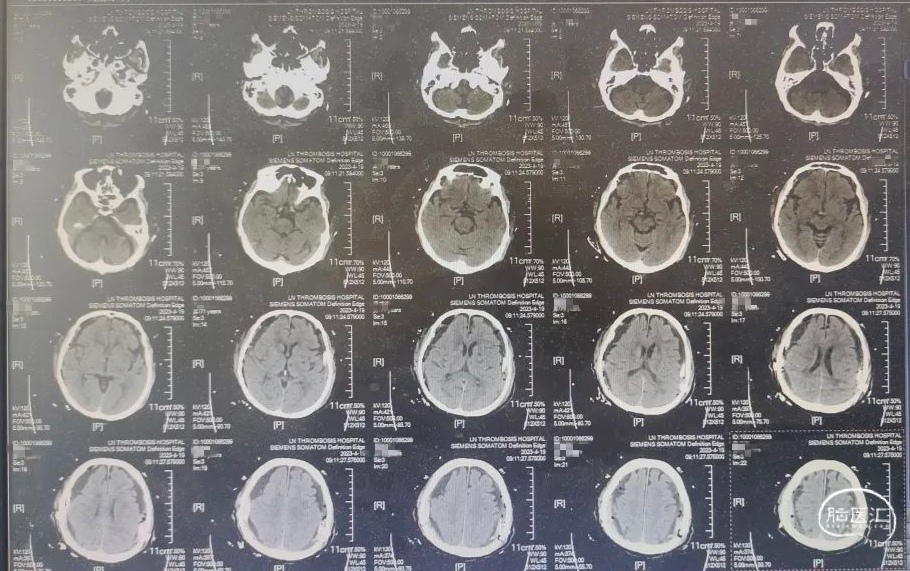

术前CT

患者双侧亚急性硬膜下血肿,血肿混杂密度,神经内镜下血肿清除术。

术后复查